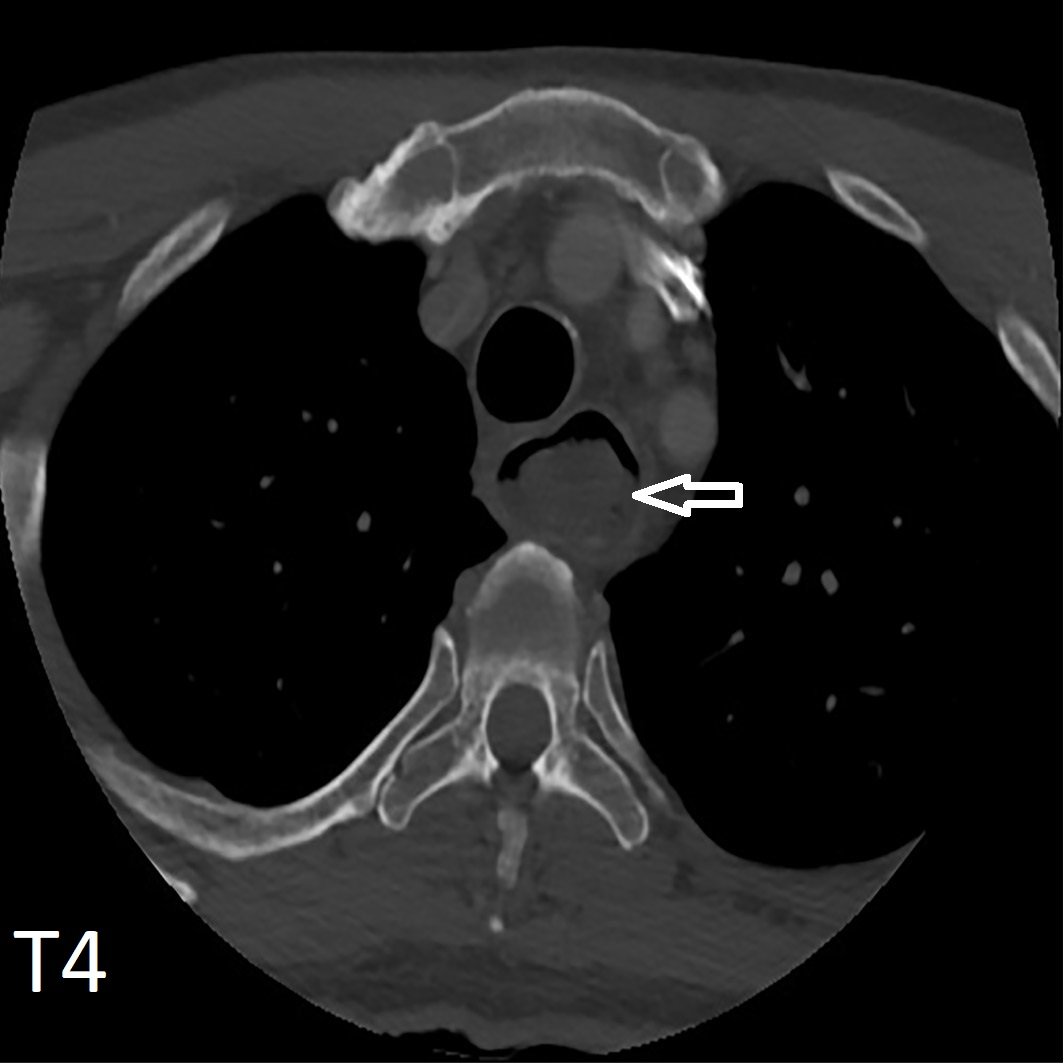

Is The Esophagus Wall Thick. The esophageal muscles are not uniform. The esophagus a is rather straight tube communicating the pharynx and the stomach.

Except at the upper esophageal sphincter, the. Smooth muscles can contract slowly. It is located in the neck and chest cavity (thorax).